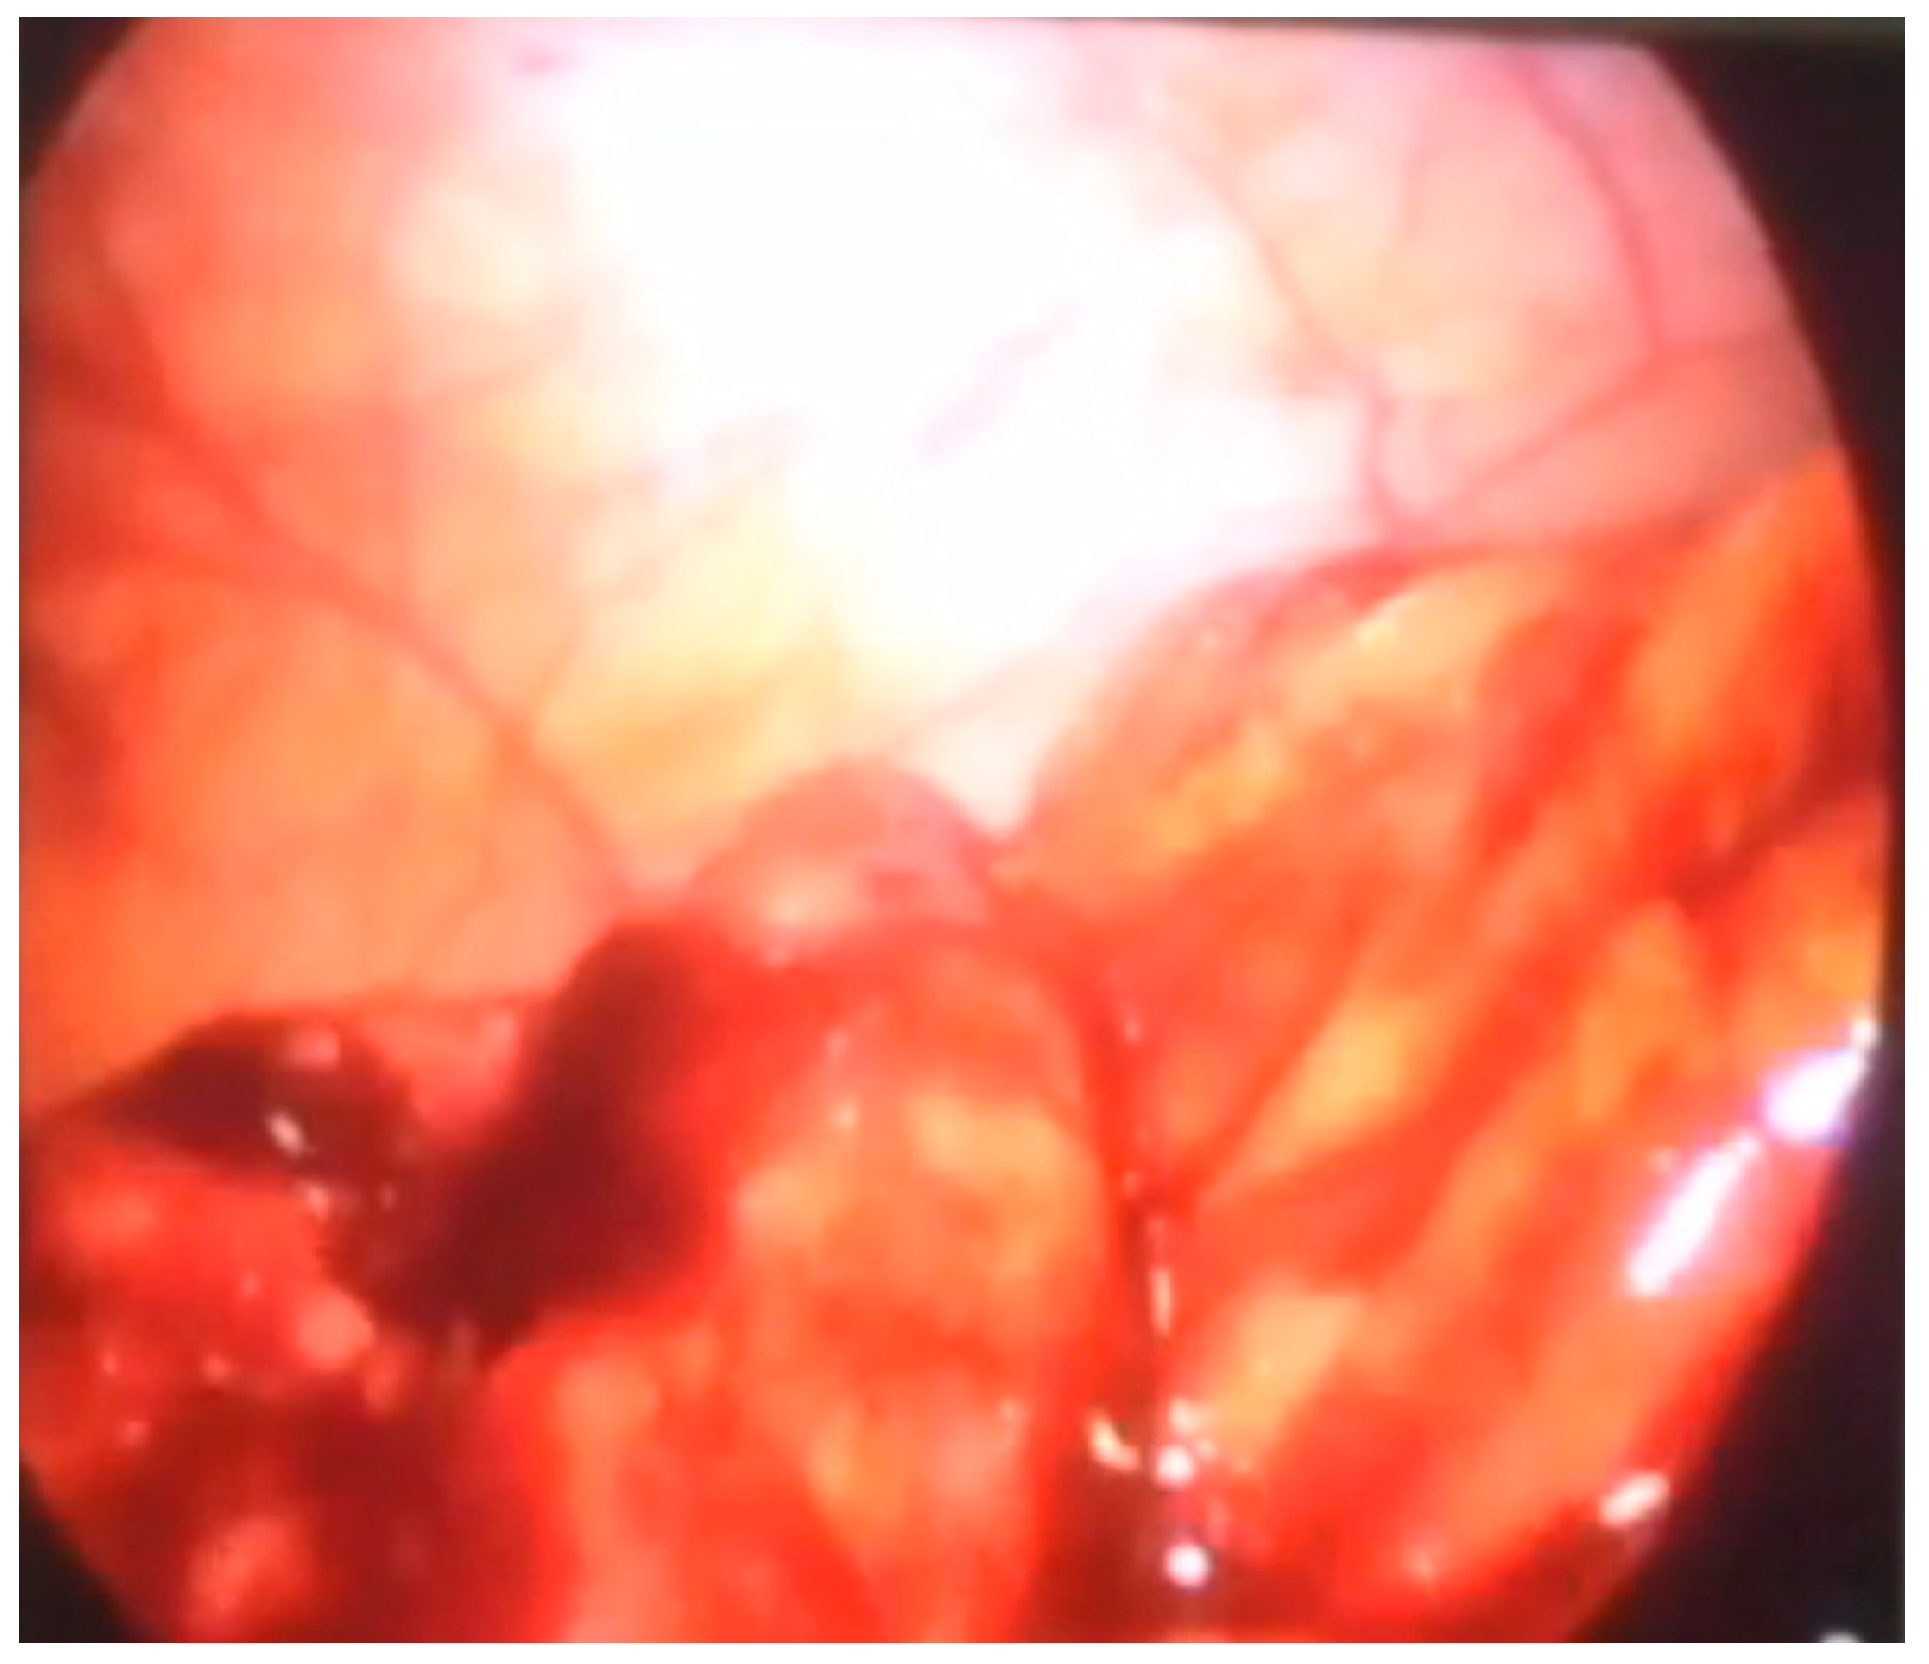

Another patient was hospitalized at our Institute due to abdominal pain and blood in a stool. A colonoscopy revealed a polyp in the region of the cecum. A simultaneous laparoscopic–endoscopic “rendezvous” polypectomy was performed, and the polyp was sent for histologic examination (Figure 6A). The polyp was on the long loop (Figure 6B) and the main difficulty was to differentiate the polyp from the edematous ileocecal (Bauhin’s) valve (Figure 7). The enterotomy on the cecum was sutured with direct intracorporeal sutures in two layers. The histology confirmed the diagnosis of a juvenile polyp.

Figure 6.

(A) Laparoscopic excision of the cecum polyp, (B) polyp on the long loop.

Figure 7.

Edematous ileocecal valve that could be missed for polyp.